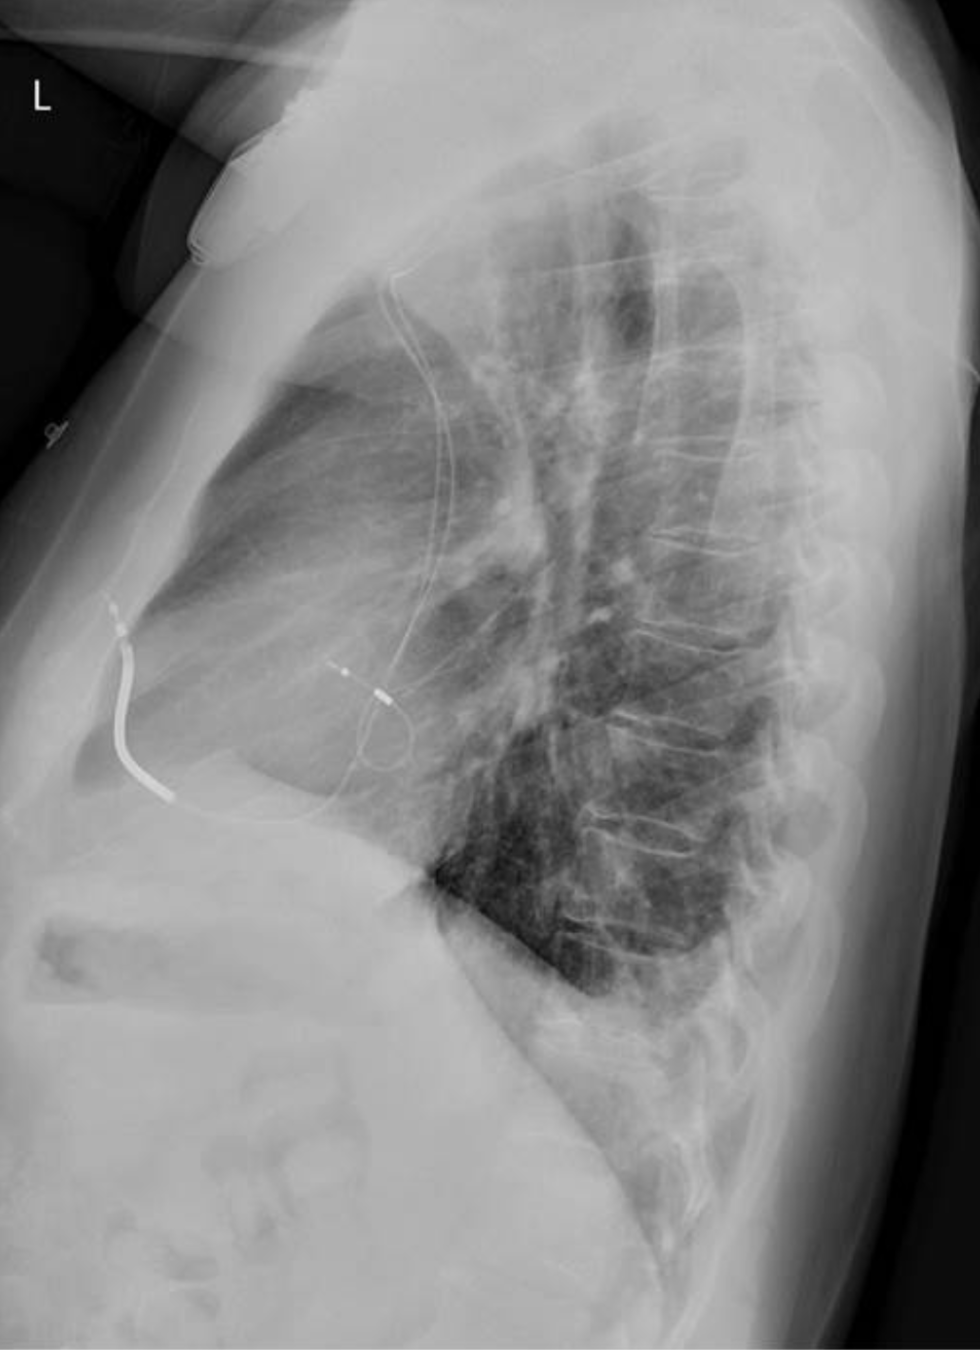

Diaphragmatic Hernia